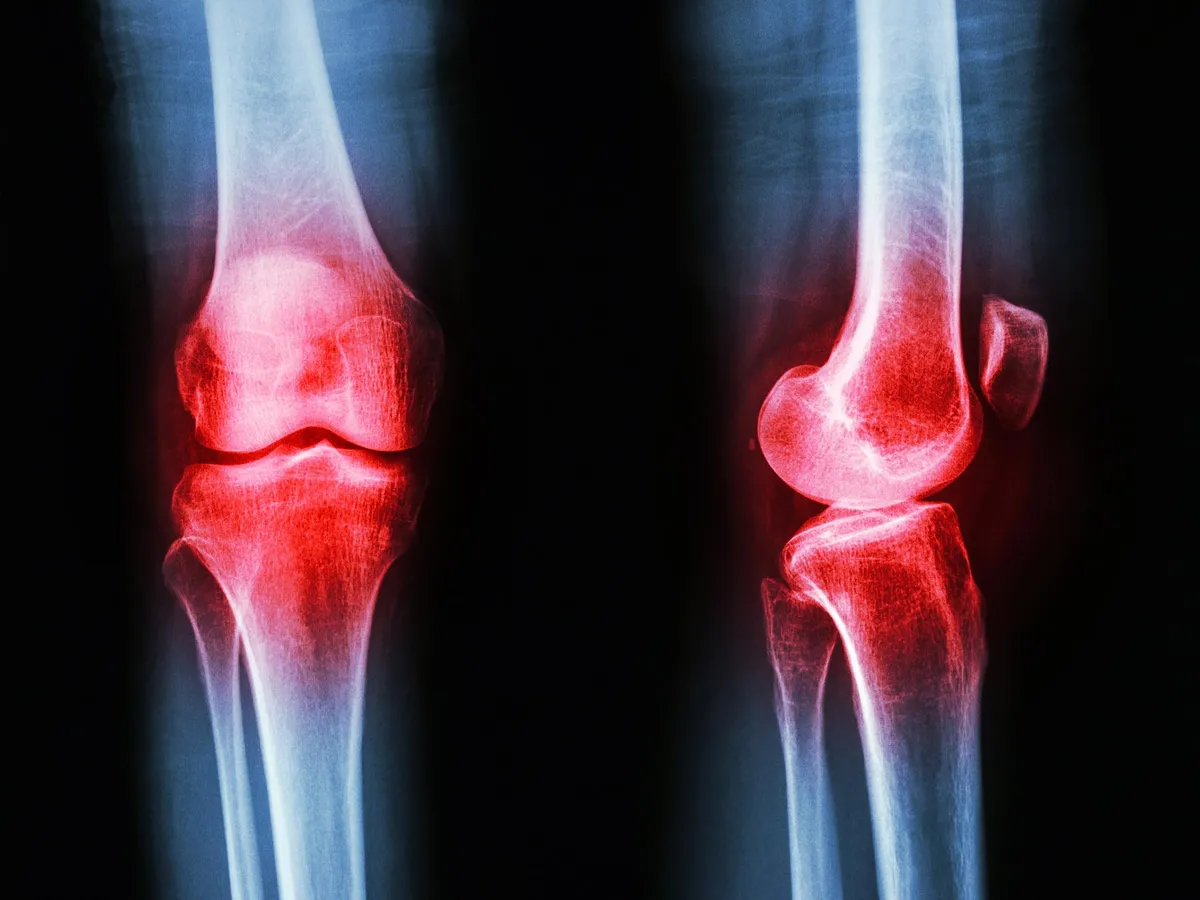

Nearly 600 million people live with osteoarthritis right now. By 2050, that number could climb toward a billion. The condition creeps into joints quietly — cartilage thins, bone weakens, movement becomes harder. And yet the most effective treatment isn't a pill waiting in a pharmacy or a surgeon's scalpel. It's movement itself.

Osteoarthritis isn't just about worn-out cartilage — that's the old story. Researchers now understand it as a whole-joint disease. It affects the fluid inside the joint, the bone underneath, ligaments, surrounding muscles, and even the nerves that control movement. Therapeutic exercise reaches all of these at once.